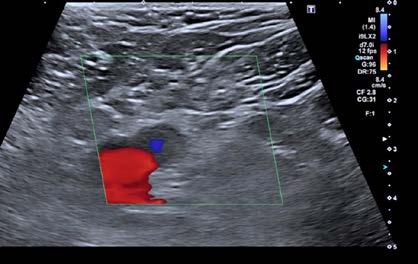

Se realizó una tomografía computarizada (TC) con contraste de forma emergente, que mostró una disección aórtica iatrogénica tipo A focal de origen en la zona 0 del cayado con extensión al tronco braquiocefálico derecho (1) sin afectar al resto de troncos supra-aórticos, cayado o aorta descendente (Figuras 1 y 2); además del hematoma

Figuras 1 y 2: Prótesis aórtica migrada y disección aórtica focal tipo A, de origen en la curvatura menor del arco aórtico (zona 0) hasta la bifurcación de la arteria braquiocefálica derecha; sin afectación de del resto de troncos supra-aórticos, del resto del cayado aórtico o de la aorta descendente.